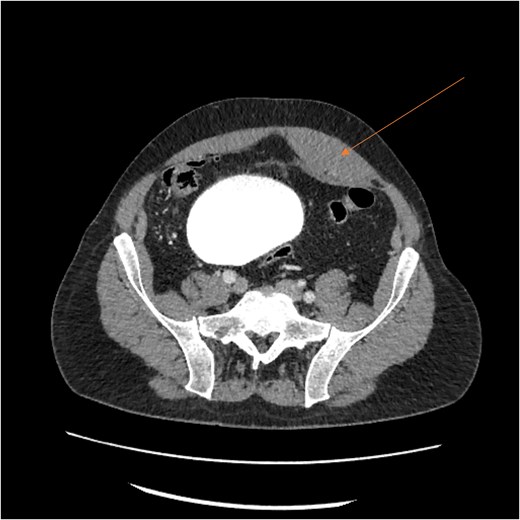

Laboratory results showed thrombocytopenia and erythrocytosis, with a hemoglobin level of 18.6 g/dl and platelets at 840 00/μl. A CT scan of the abdomen and pelvis was ordered to rule out malignancy or paraneoplastic syndrome causing the VTE (Fig. 1). The CT showed no lesions suspicious for malignancy but revealed a left RSH, managed conservatively.